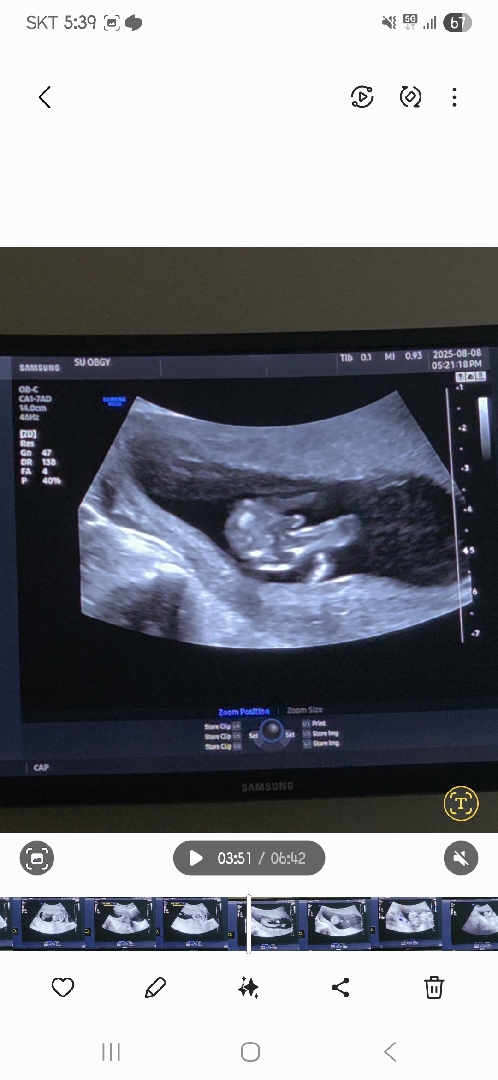

와우 이건 아들이네요

13주 4일 성별

이정도까지 잘보이면 빼박인가요..?;;ㅎ 반전은 없겟죠...?

ㅋㅋㅋㅋㅋㅋ인정하기로 했습니다...🥲